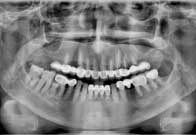

(10) Dental Implant - Full Mouth

Before Treatment

After Treatment

Patient came with a problem in chewing food and multiple loose teeth in upper and lower jaw and was interested in getting a whole new set of teeth in both the jaws. So after removal of all the weakened teeth and placement of multiple implants, he was given implant supported bridge.